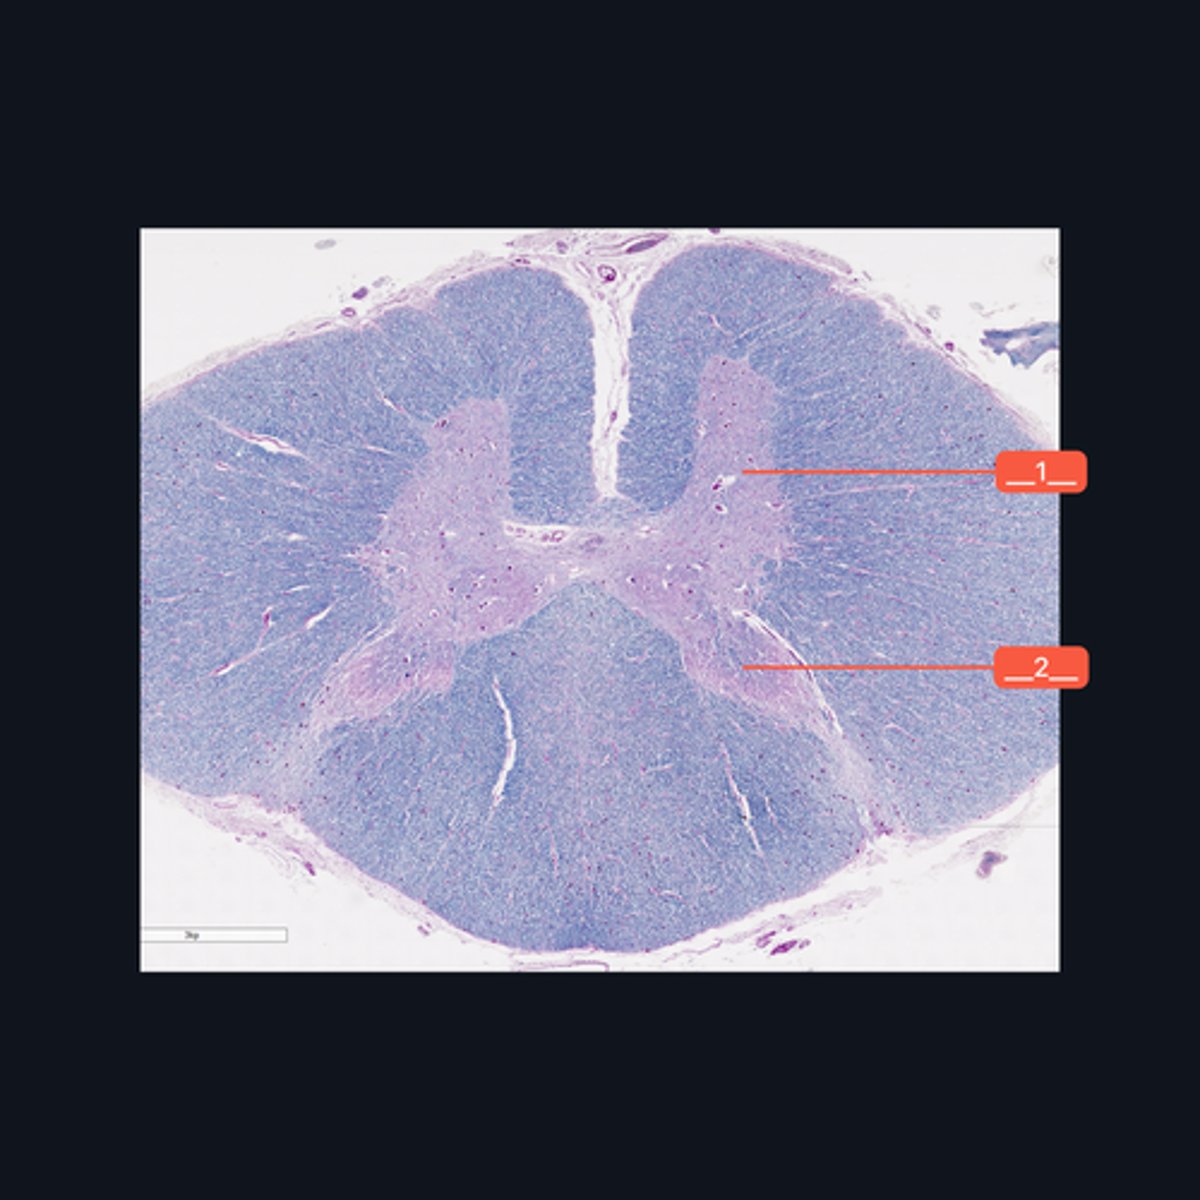

Identify the pointed region in the spinal cord

(1) Ventral Horn, (2) Dorsal Horn

Identify the pointed regions of the gray matter of the spinal cord

Sacral region

Identify the region of the spinal cord in the given image.

(top to bottom)

Ventral median fissure

White matter

Ventral horns

Central Canal

Central commissure

Dorsal midline sulcus

Dorsal horns

Identify the parts of the sacral region of the spinal cord.

FALSE

T or F: The white matter in this region of the spinal cord is larger than the white matter in the thoracic region of the spinal cord.

Upper Cervical region

Identify the region of the spinal cord in the given image.

(top to bottom)

White matter

Ventral horn of gray matter

Central canal

Central Commissure

Dorsal horn of the gray matter

Dorsal Midline Sulcus

Identify the structures found in the upper cervical region of the spinal cord.